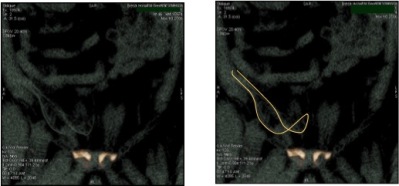

En estas imágenes se aprecia la malla doblada sin expandirse completamente en el espacio preperitoneal.

La evaluación del anillo de memoria de poliéster de la malla mediante el tac 3D nos permite comprobar la expansión y el posicionamiento de las mallas sin añadir agrafes u otros artefactos.